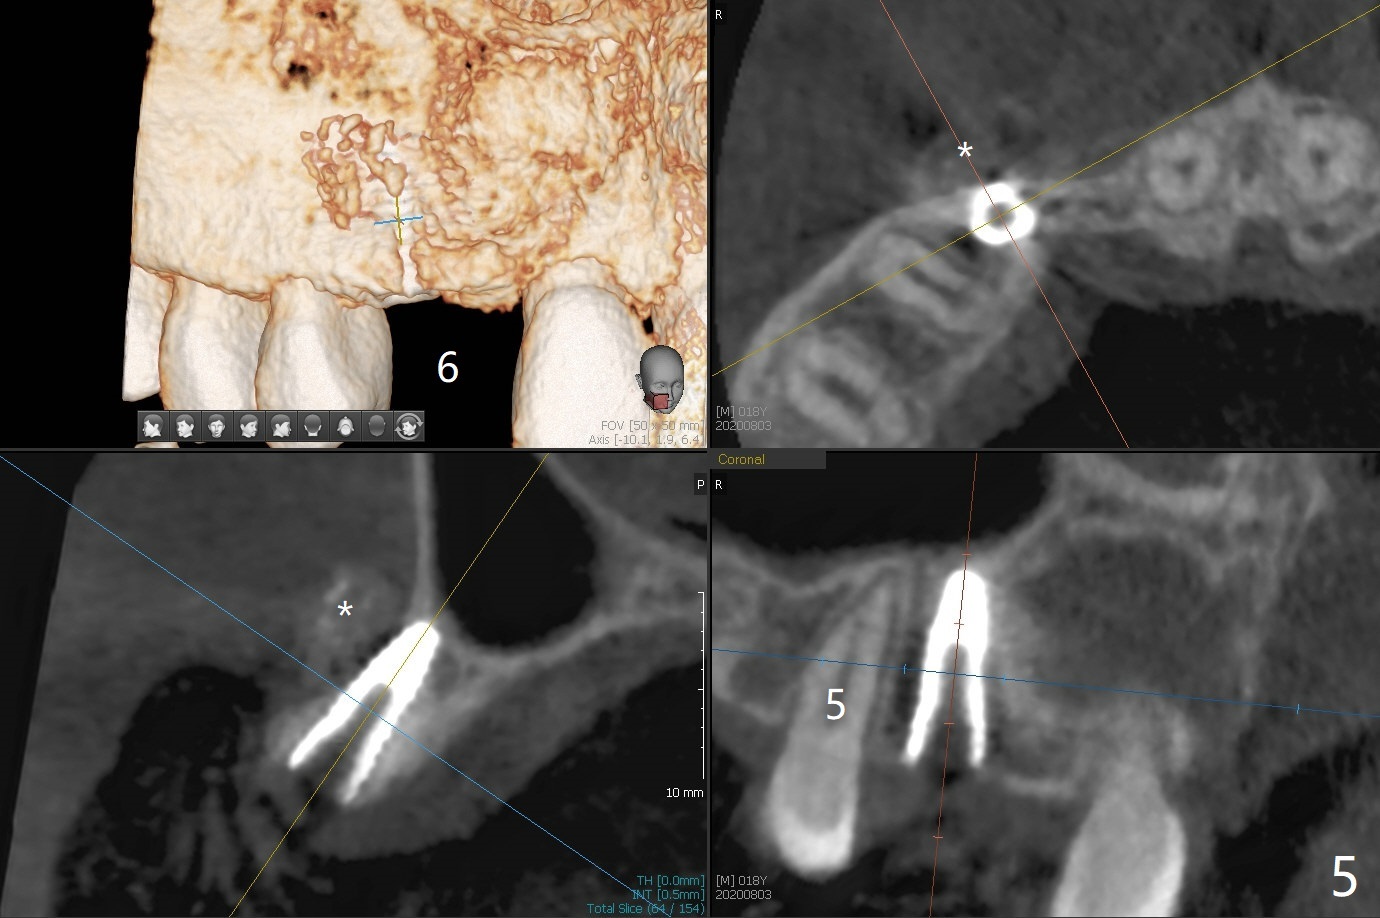

18岁男,本月底到外州上大学,急于十九岁前完成治疗,保险可以多付些。术前检查显示双侧尖牙(图一,二 6,11)根尖,侧切牙牙槽嵴萎缩(*),尖牙、侧切牙之间颊侧做垂直切口,骨膜下潜行分离,在尖牙根尖隧道植骨,然后使用导板,植入窄植体(图四至六),接近或者穿过上颌窦底板(图三,四箭头),骨粉(粘性骨块做的不成功,图五,六 *)好像覆盖暴露的螺纹。再次补充隧道骨粉后,放置修复基台(图七,八),调整后(图九),取模做临时悬臂桥,临床上有些困难分配尖牙,侧切牙比例。术后4个月左侧植体愈合正常(图十,十一),而右侧感染。